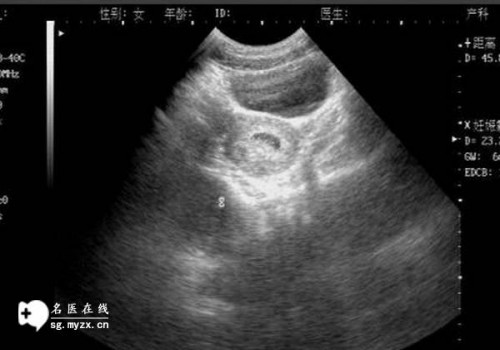

一般需要在5-7天进行囊胚移植,如果不符合新鲜周期移植的条件,那么第三个月经周期一般需要冷冻胚胎移植,囊胚需要体外培养5-6天,此时如果子宫内膜情况在10mm左右,没有腹水,激素水平难以稳定,可以直接移植,如果不符合移植的条件,一般需要冷冻,等子宫内膜条件好一点再移植,所以每个患者的移植时间是不一样的。

综上所述,二代试管取卵后囊胚移植的时间需要根据个人的实际情况来考虑,通常新鲜周期囊胚移植是在取卵后的第5-7天,当然也需要身体条件符合移植的要求。